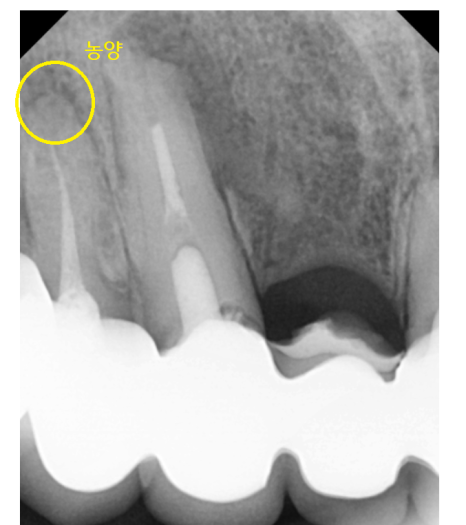

큰 사진에서 의심되는 부분을

추가적으로 검사해 보았더니

어이쿠야..

뿌리 끝에 농양으로

주변 뼈가 녹았네요.

23.06.07

이미 신경치료까지 되어있는 상황이라

좋지 않았지만

살려볼 수 있는 1% 가능성이라도

확인하기 위해 ct까지 찍어보았습니다.